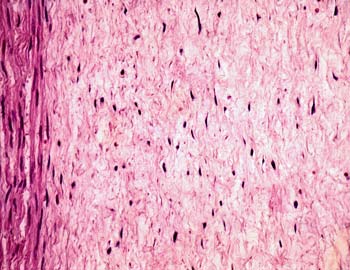

Visión general: presentamos una sección transversal de un cordón.

Observareis el tejido epitelial en el contorno, revistiendo la superficie

externa y tapizando la luz de los vasos, tanto de las tres grandes estructuras

centrales como de pequeños capilares dispersos por un abundante

tejido con mucha sustancia intercelular y pocas células, que se

denomina conjuntivo mucoso. Las fibras, fundamentalmente de colágena,

son muy finas, y el compartimento mas notorio es la sustancia fundamental,

glicoproteinas, proteinglicanos dispersos en agua.

Visión específica: se observan

en el interior de los tres grandes vasos centrales el contenido hemático

y alrededor un refuerzo de fibras musculares lisas. Ya por fuera de los

mismos disminuye la coloración dado el carácter amorfo de

la sustancia fundamental. Ello nos permitirá con facilidad ver

las finas fibras de colágena, de carácter eosinófilo,

y los cuerpos de las células fibroblásticas como elementos

elongados o estrellados.